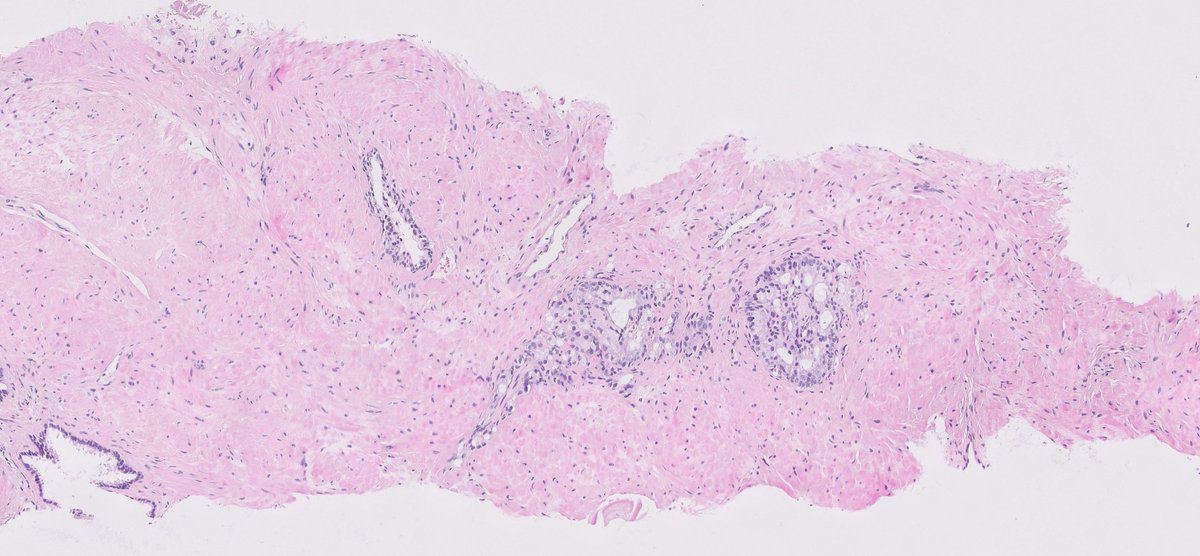

@smlungpathguy

Thoracic masses. Can you guess how many immunostains were done and why? #pathology #pulmpath